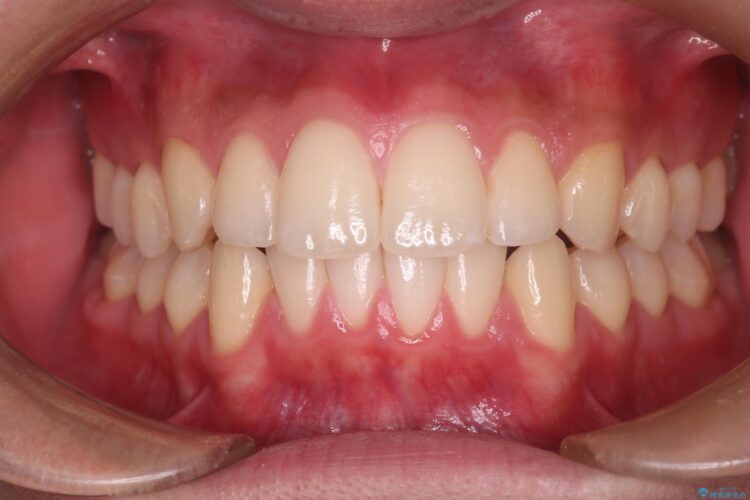

上の前歯が出ているのが気になるとご来院された患者様です。

治療後について

患者様はシミュレーション通りに歯が動くのかと心配されていました。

可能な限り計画通りに歯を動かすために、マウスピース1枚あたりの使用時間を長めに使っていただきました。

そのため、多少治療期間が延びましたが、リファイメント(マウスピースの再発注)なしで終了することができました。